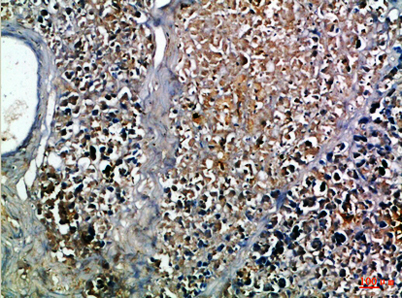

Insulin rabbit pAb

Ref: ELK-ES8775-100μL

Recomended Dilution IHC-p 1:50-200, ELISA 1:10000-20000